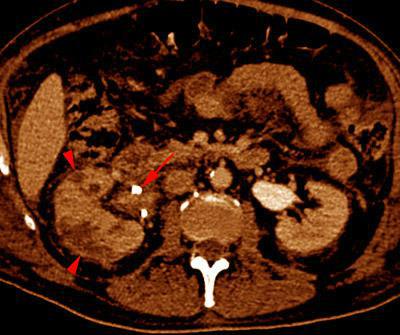

VR seccional. Visión axial caudal. Nefromegalia. Obstrucción renal derecha con catéter doble J (flecha). Múltiples lesiones hipodensas (puntas de flecha) correspondientes a abscesos renales